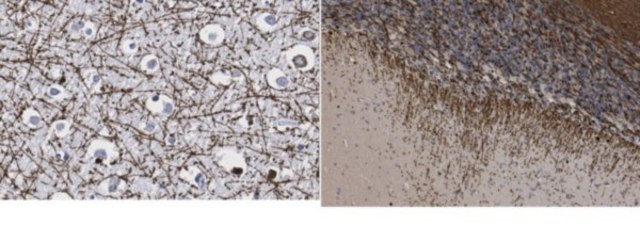

Immunohistochemistry Analysis: A 1:1,000 dilution from a representative lot detected Myelin Basic Protein in human cerebral cortex and rat cerebellum tissue sections.